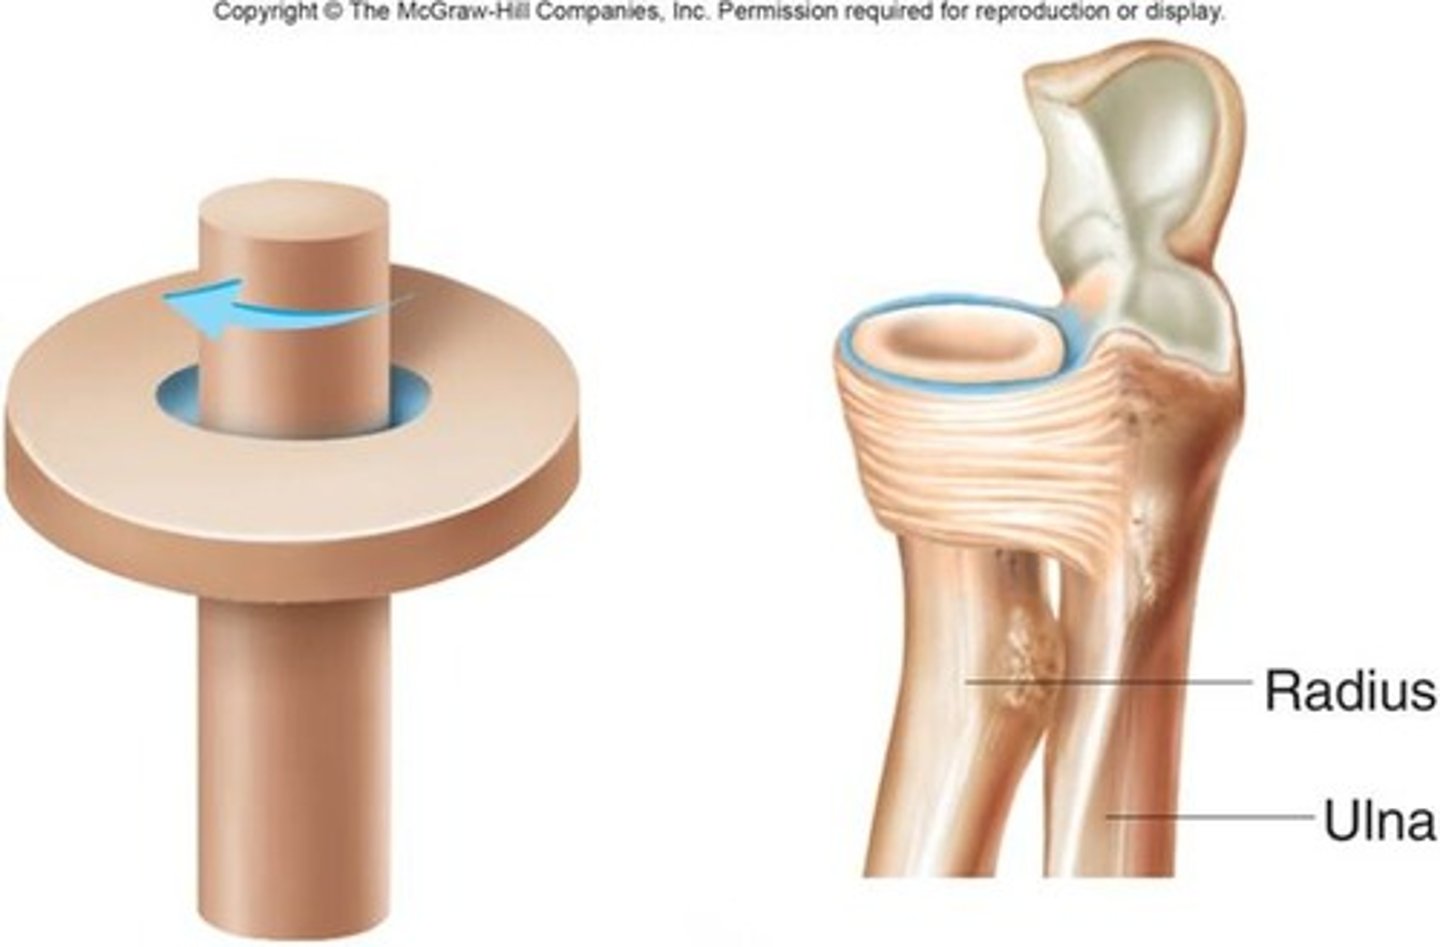

Pivot synovial joint

allow movement around one axis that passes longitudinally along the shaft of the bone

-permits rotation

ex:atlanto-axial joint